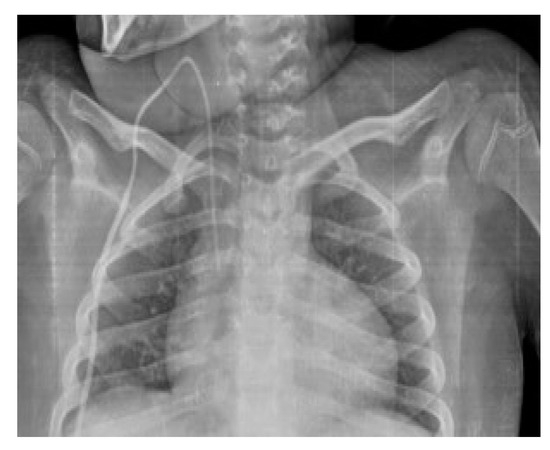

Conventional Radiology Evaluation of Neonatal Intravascular Devices (NIVDs): A Case Series

3. Results